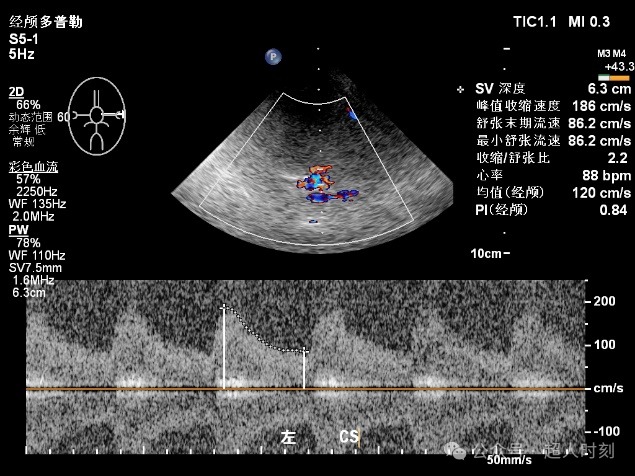

图5g左颈内动脉虹吸部狭窄血流频谱(VP:186cm/s)